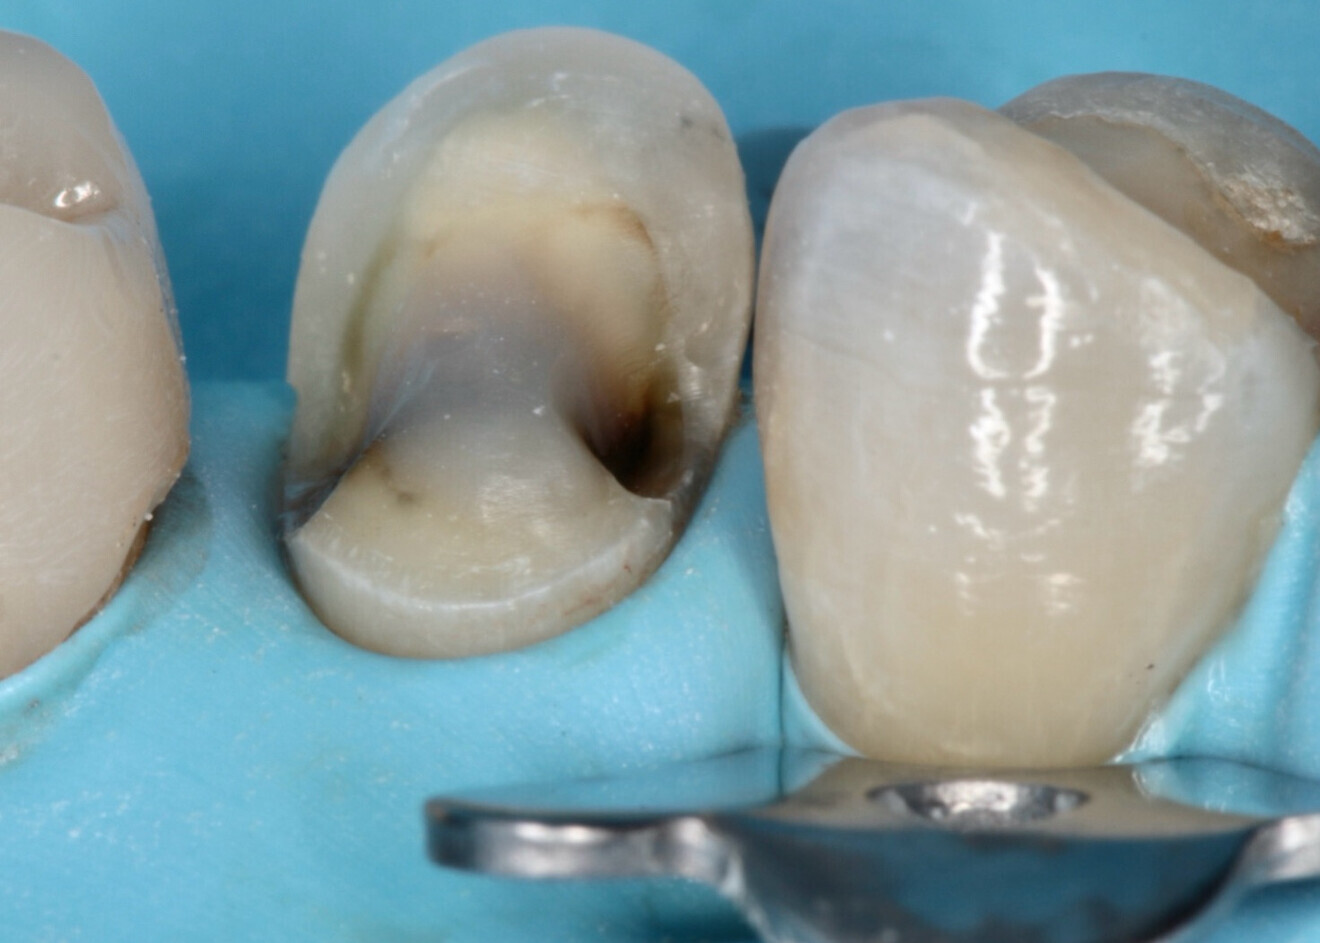

Fig. 5 : La préparation dentaire pour l’assemblage.

Bien que les restaurations adhésives présentent de nombreux avantages, elles ne sont pas toujours adaptées à toutes les situations cliniques. Il est essentiel de distinguer les cas où une préparation adhésive est préférable de ceux où les méthodes traditionnelles de rétention mécanique restent plus appropriées. Les restaurations collées sont idéales pour les patients avec des dents présentant des structures suffisamment solides, pour bénéficier d’une liaison chimique sans compromettre la résistance (Fig. 5). Cependant, dans des cas de perte de structure dentaire importante, ou lorsque la zone de restauration est trop étendue, une couronne complète avec une préparation traditionnelle pourrait être plus indiquée.